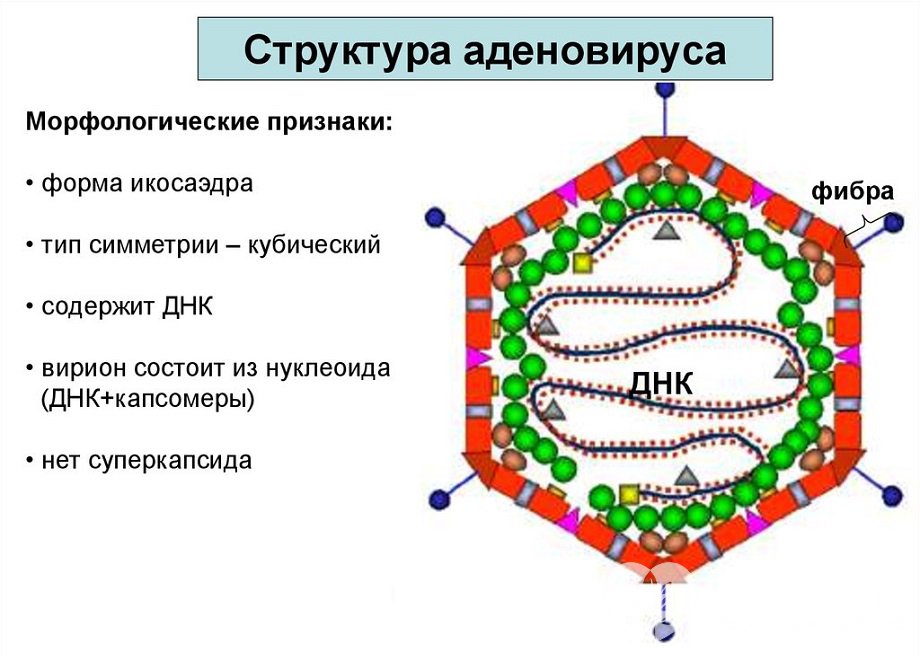

Структура аденовируса

Структура аденовирусаАденовирусы впервые были выделены в 1953 году от детей, больных атипичной пневмонией и острой респираторной вирусной инфекцией, протекающих с явлениями конъюнктивита У. Роу. В последующем многочисленные исследования на животных, показали онкогенность аденовирусов, т. е. их способность провоцировать развитие злокачественных опухолей.

Возбудителями аденовирусной инфекции выступают ДНК-содержащие вирусы, относящиеся к роду Mastadenovirus семейства Adenoviridae. В настоящее время специалистами описано свыше 100 серологических типов аденовирусов, около 40 из них были выделены от людей.